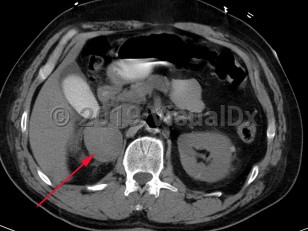

Pheochromocytoma (PCC) is a rare catecholamine-secreting neoplasm of adrenal origin; when it is extra-adrenal, it is referred to as paraganglioma. PCC is known as the "great masquerader" because of its similarity in clinical presentation to many other conditions. Up to 15% of patients may be asymptomatic. The most common presenting symptoms are hypertension (including labile hypertension), palpitations, increased sweating, severe headache, tremors, pallor, and dyspnea. Atypical symptoms include anxiety, abdominal pain, nausea, vomiting, constipation, insomnia, and weight loss. The prevalence of PCC in patients with hypertension is less than 0.2%. Rarely, paragangliomas may occur in the heart. Cardiovascular complications of catecholamine excess are rare but can lead to stress cardiomyopathy. Clinical presentation is characterized by transient duration of symptoms (eg, 15-20 minutes) that may recur several times a day. Physical exertion (moderate to extreme exercise) or bowel movements may provoke symptoms. Sometimes a pheochromocytoma is found incidentally during a workup.

The majority of PCCs are intra-adrenal and solitary. Approximately 10% of all catecholamine-secreting tumors will be malignant. PCC may occur at any age but has the highest prevalence in individuals aged 20-50 years.